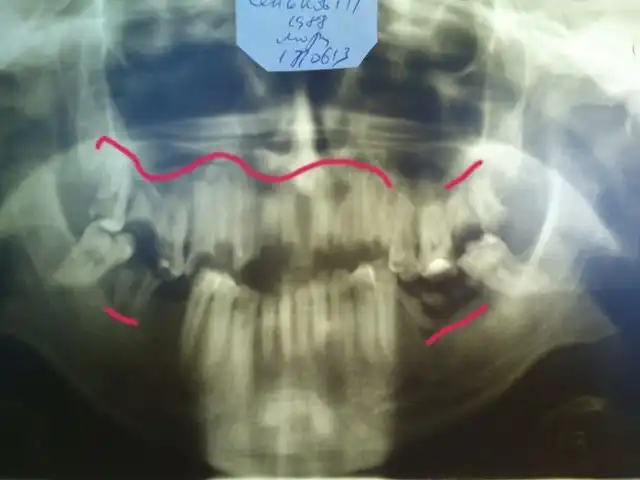

А это его панорамная рентгенограмма. То, что обвел красным, надо удалять. В 25 лет этому парню надо ставить съемные пластиночные протезы. Это такие, как вы видели у своих бабушек и дедушек в стаканах на тумбочке у кровати…